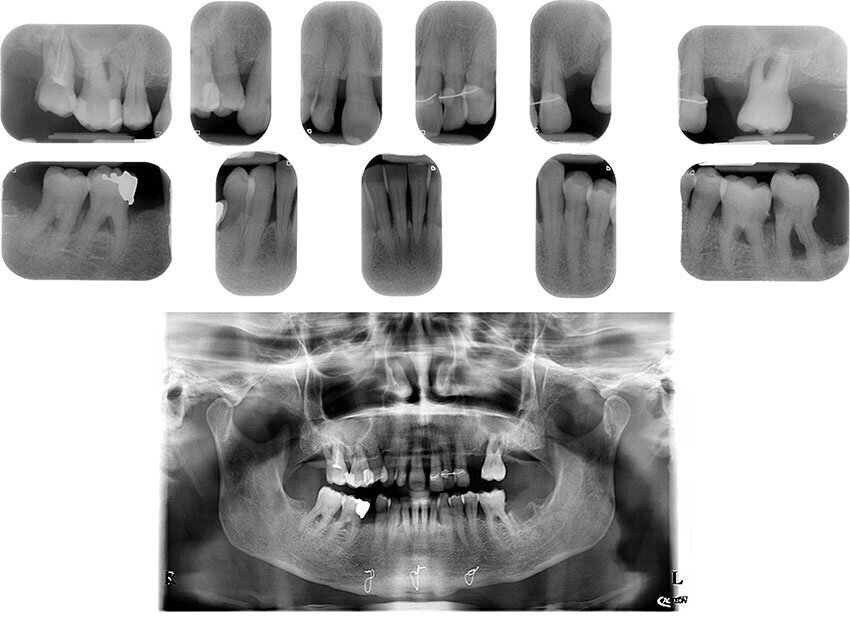

Fig. 3_Dopo l’estrazione dei denti 1.6, 1.7, 2.6.

Fig. 50_Controllo radiografico.